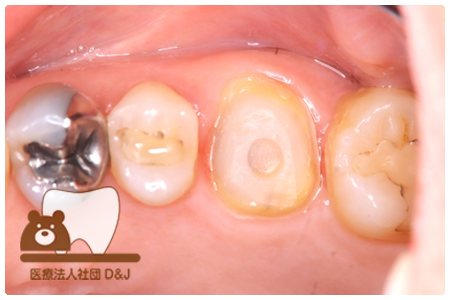

症例8フルジルコニアクラウン

治療前

治療中

治療後

29歳 女性

- 治療内容

- 銀歯からフルジルコニアクラウンへの修復

- 治療期間

- 根の治療含め3か月

- 費用

- 自費

フルジルコニアクラウン:77,000円(税込)

- その他の治療の費用は含まれておりません。

- リスク・副作用

- 強い衝撃が加わると欠けたり割れたりする可能性があります。また、噛み合わせの状態によっては脱離や周囲の歯への影響が出ることもあります。